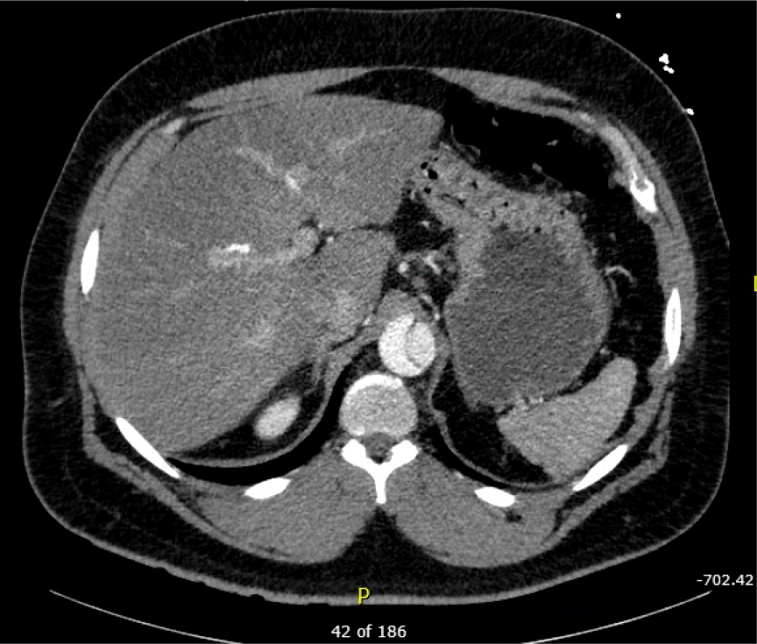

Patient’s initial EKG showed ST elevation in anterior leads, with possible ST depression in inferior leads, and T wave inversion in lateral leads. Given the patient’s clinical presentation and appearance, there was concern for ongoing ischemia. Based on the patient’s history of pain radiating into the abdomen and severe hypertension, there was additional concern for aortic dissection. This led to the cancelation of the catheterization lab activation. Slices of his computed tomography (CT) scan are shown below, revealing a severe type A aortic dissection, dissecting from the coronary arteries to the bilateral iliac arteries. Patient was started on nitroprusside and esmolol infusion and transferred emergently for cardiovascular surgery. He was discharged from the hospital in good condition less than one week later following an uncomplicated post-operative course.